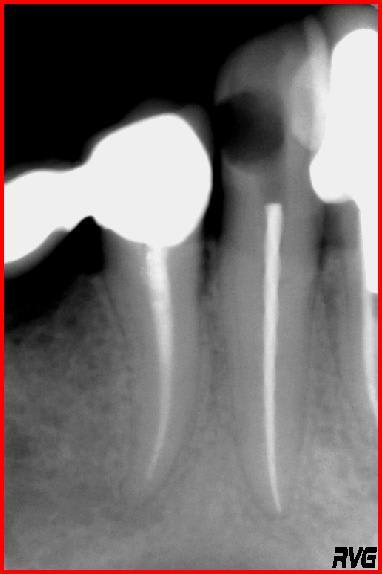

Bon ... j'ai voulu être économe en tissu ... je suis passé par la cavité distale ... protaper F2 un peu trop angulé ... et là c'est le drame.

Ma question est la suivante : quelle est votre méthode pour sortir cet instrument de la canine ?

t'as quand même du bol: une canine bien droite et bien épaisse, une fracture bien haute.

C'est etonnant, je n;ai jamais vu un instrument fracture comme ca ; vous etes vraiment passe a travers la carie pour faire le traitement endodontique ou c'est une blague ???

J'exagère un peu quand je dis que je suis passé par la carie. L'ouverture était certe insuffisante mais je suis quand même étonné que ça ait cassé aussi facilement.

PS : l'instrument était neuf et j'utilise l'endomaster d'ems comme moteur d'endo. Il a cassé à la limite entre la partie lisse et la partie torsadée.